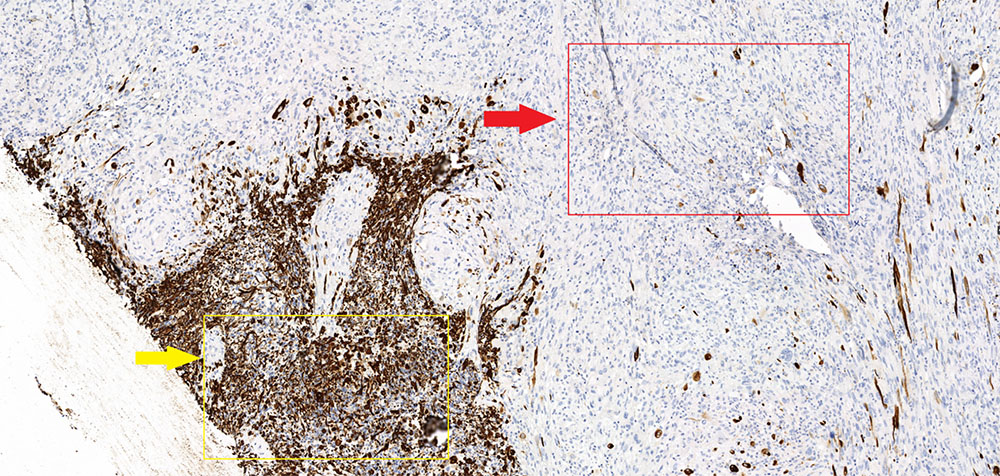

Маркер GFAP (специфичный глиальный фибриллярный кислый белок) – демонстрирует характерную выраженную экспессию в глиальной части опухоли (желтая стрелка) и полное отсутствие экспрессии в саркоматозной (красная стрелка). Кроме того в данном микропрепарате стоит отметить отчетливое преобладание саркоматозной части над глиальной.